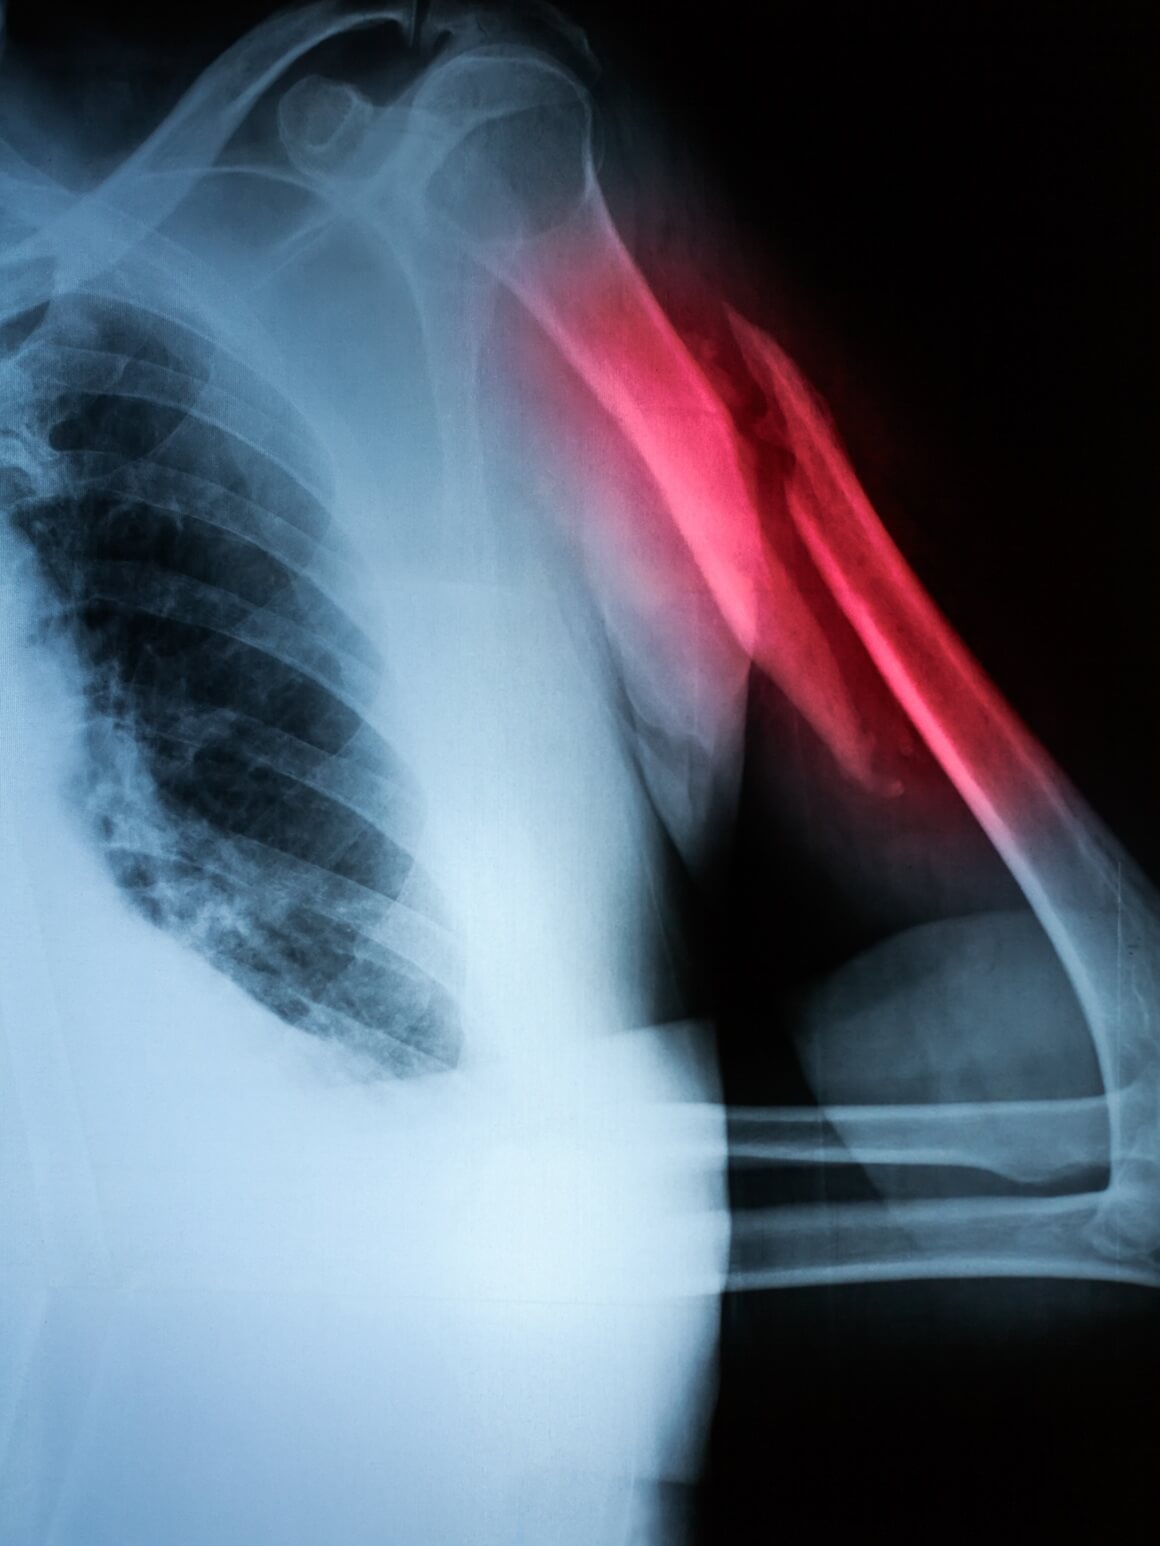

- humerus (nadlaktična kost) – pseudoartroza se često javlja u dijafizi humerusa; razlog je pokretljivost ramena i teško održavanje stabilne imobilizacije, što dovodi do trajne boli i slabosti ruke